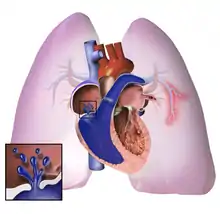

Right ventricle (on left side)

The pathogenesis of pulmonary arterial hypertension (WHO Group I) involves the narrowing of blood vessels connected to and within the lungs. This makes it harder for the heart to pump blood through the lungs, as it is much harder to make water flow through a narrow pipe as opposed to a wide one. Over time, the affected blood vessels become stiffer and thicker, in a process known as fibrosis. The mechanisms involved in this narrowing process include vasoconstriction, thrombosis, and vascular remodeling (excessive cellular proliferation, fibrosis, and reduced apoptosis/programmed cell death in the vessel walls, caused by inflammation, disordered metabolism and dysregulation of certain growth factors).[26][27] This further increases the blood pressure within the lungs and impairs their blood flow. In common with other types of pulmonary hypertension, these changes result in an increased workload for the right side of the heart.[15][28] The right ventricle is normally part of a low pressure system, with systolic ventricular pressures that are lower than those that the left ventricle normally encounters. As such, the right ventricle cannot cope as well with higher pressures, and although right ventricular adaptations (hypertrophy and increased contractility of the heart muscle) initially help to preserve stroke volume, ultimately these compensatory mechanisms are insufficient; the right ventricular muscle cannot get enough oxygen to meet its needs and right heart failure follows.[15][27][28] As the blood flowing through the lungs decreases, the left side of the heart receives less blood. This blood may also carry less oxygen than normal. Therefore, it becomes harder and harder for the left side of the heart to supply sufficient oxygen to the rest of the body, especially during physical activity.[29][30][10] During the end-systolic volume phase of the cardiac cycle, the Gaussian curvature and the mean curvature of right ventricular endocardial wall of PH patients was found to be significantly different as compared to controls.[31]